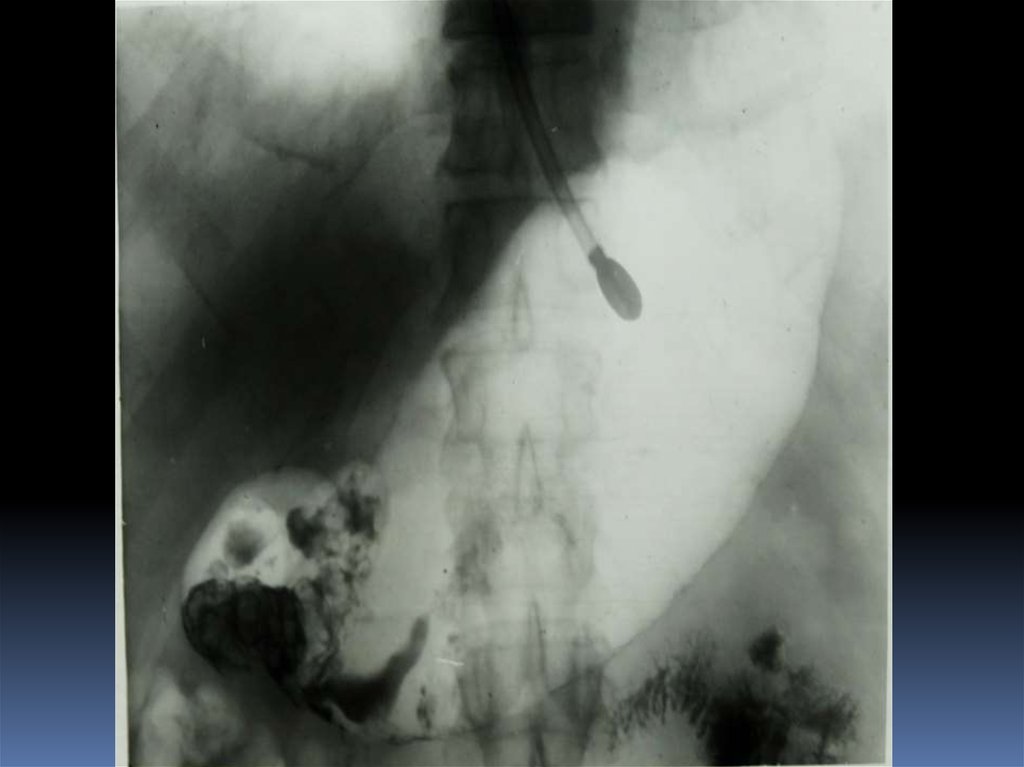

54. Редкие случаи из практики

55.

56.